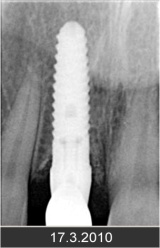

Klasickým příkladem a indikací pro použití implantátu je ztráta jednoho zubu (v tomto případě v předním – frontálním úseku) v jinak zdravém, nepoškozeném chrupu.

Nejčastější příčinou takové ztráty je sportovní nebo dopravní úraz.